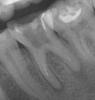

omeza Опубликовано 17 июня, 2010 Поделиться Опубликовано 17 июня, 2010 Добрый вечер! На 6 зубе гранулемы(снимок прелагаю), хирург говорит что надо удалять, ортопед лечила метапексом, но зуб от него стал ужасно болеть...Подскажите, есть ли другие пути решения или только на удаление? unsure.gif Ссылка на комментарий

Мартовский Опубликовано 17 июня, 2010 Поделиться Опубликовано 17 июня, 2010 Добрый вечер! На 6 зубе гранулемы(снимок прелагаю), хирург говорит что надо удалять, ортопед лечила метапексом, но зуб от него стал ужасно болеть...Подскажите, есть ли другие пути решения или только на удаление? unsure.gifПуть решения стандартный - перелечить каналы и посмотреть в динамике. И совет стандартный - найти врача, который сможет это сделать. Ссылка на комментарий

pawa Опубликовано 17 июня, 2010 Поделиться Опубликовано 17 июня, 2010 Надо лечить. Но зуб не простой... Ссылка на комментарий

doktorenok Опубликовано 18 июня, 2010 Поделиться Опубликовано 18 июня, 2010 Надо лечить. Но зуб не простой... И лечить должен не ортопед, а доктор имеющий большой опыт и знания в сложной эндодонтии Ссылка на комментарий